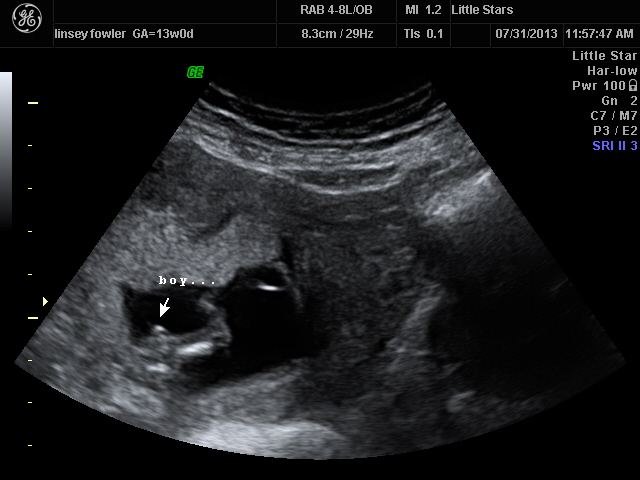

Was told 100% this was a boy. I have two little girls so we are ecstatic! Im afraid to be too excited since it is so early on! We have never found out before 20 weeks! Anyone else think this is a boy???Attachment 12823 Attachment 12824

The first image is of the baby's legs curled to the side. She said those were his boy parts sitting in the back.

I was excited that day but now Im overanalyzing and nervous!

Im not sure if you can zoom in or not but in the 4d image, you can see a "stick" and thats what made her say shes 100% sure. Ive come up with a million other things it could be! haha!